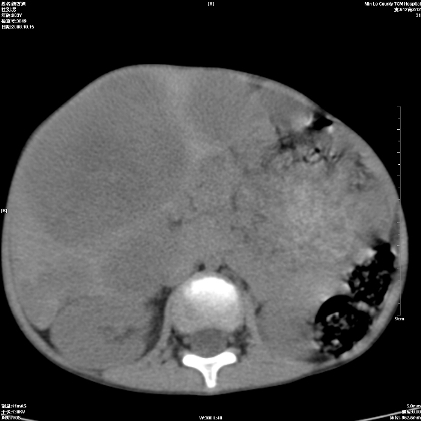

标题: PED1609:男性,3岁。彩超示肝Ca. [打印本页]

标题: PED1609:男性,3岁。彩超示肝Ca.

3岁;肝低密度灶;有钙化;有转移灶;考虑肝母细胞瘤;查afp

考虑神经母细胞瘤并肝转移